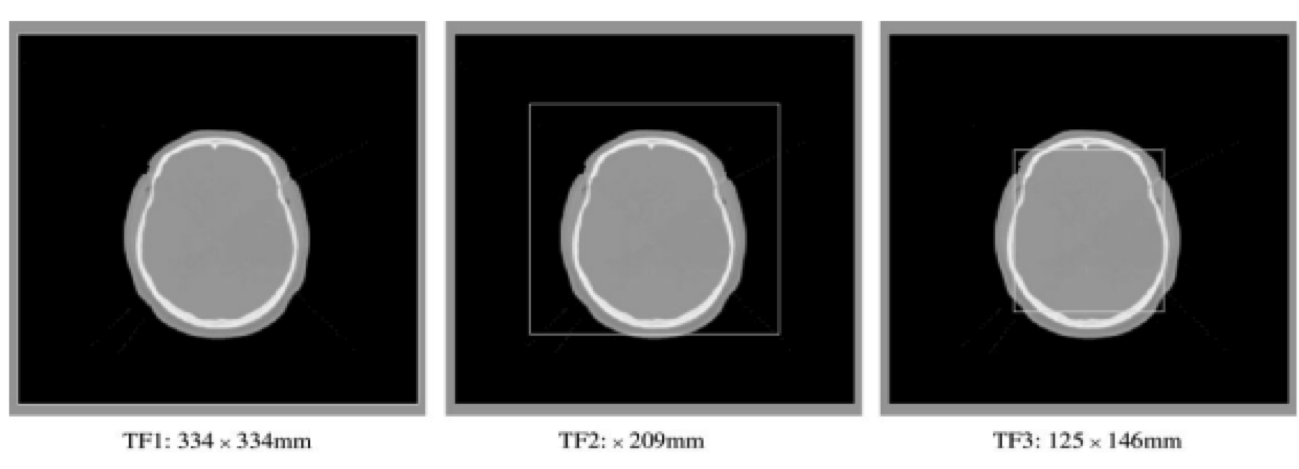

2.3.2 Capture Range Experiment

The aim of these experiments was to examine the behavior of the registration algorithm using different measures when it is presented along with clinical data with varying fields of view. In this case we concentrated on recovering rigid registration parameters as the trans-axial field of view. Varying the in-plane field of view determines the proportion of the image exhibiting values corresponding to air in the two modalities. In order to look at the effect this has on the registration measures; an image set (patient 5 of the Vanderbilt study) was be truncated in-plane at three levels to produce three pairs of images to register. The fields of view selected (labeled TF1, TF2 and TF3) in the MRI, CT and PET images are shown in Figure 2.

To examine how robustly different levels of initial misalignment may be recovered using the measures, sets of randomized starting estimates were produced. In these experiments sets of randomized transformations were used. These were derived by perturbing the rigid marker based parameters with random translations and rotations of sizes (mm, ),(mm, ), and (mm, ). These were then used as starting estimates for the optimization algorithm in each of the three measurements.